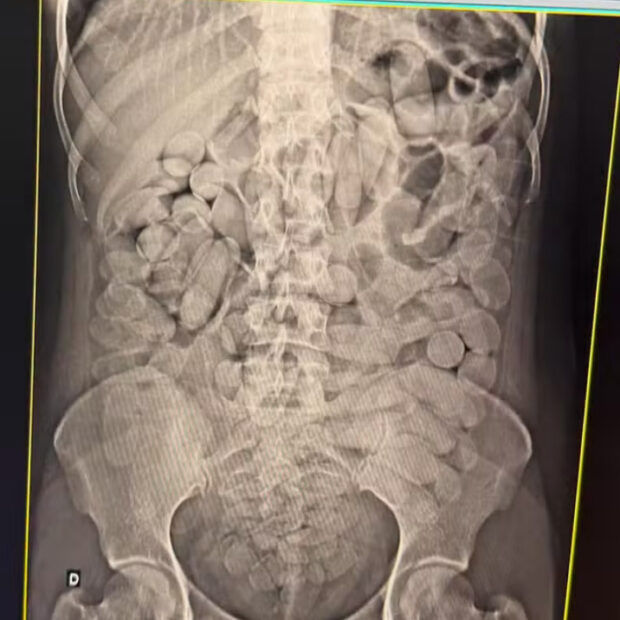

Quatro mulheres foram presas nesta segunda-feira (10/02) ao serem flagradas transportando cocaína dentro do estômago, durante uma fiscalização da Receita Federal em um ônibus clandestino, no posto de Corumbá (MS), região de fronteira com a Bolívia. Além delas, outras duas pessoas também foram detidas.

Duas das mulheres foram levadas a um hospital, onde devem expelir as cápsulas ingeridas, enquanto as outras duas foram presas em flagrante.